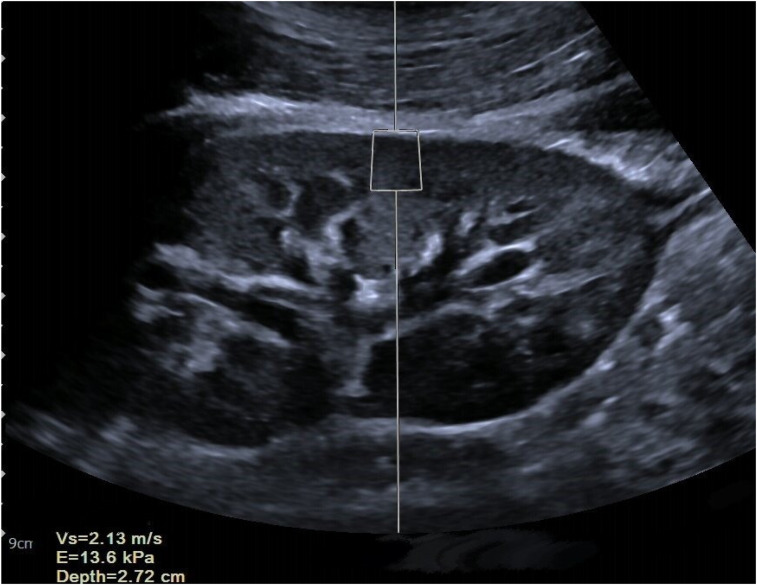

ObjectiveWe hypothesize that combining point shear wave elastography (PSWE) with clinical risk factors enables accurate renal fibrosis assessment. This retrospective study integrates PSWE with serum creatinine (Scr) and estimated glomerular filtration rate (eGFR) to develop and validate a nomogram for personalized renal fibrosis evaluation in chronic kidney disease (CKD) patients.MethodsA total of 157 patients underwent renal PSWE and kidney biopsy. PSWE measured cortical stiffness in the mid-portion of the right kidney. Feature importance was selected using elastic net regression, XGBoost, and random forest, with PSWE, Scr, and eGFR identified as key variables. Three models were established: Model 1 (PSWE + Scr + eGFR), Model 2 (Scr + eGFR), and Model 3 (PSWE). Diagnostic performance was evaluated using receiver operating characteristic (ROC) curves and area under the curve (AUC) values. A nomogram based on PSWE, Scr, and eGFR was developed for precise fibrosis risk assessment. The Hosmer-Lemeshow test and K-fold cross-validation were used to evaluate the nomogram's generalizability.ResultsModel 1 achieved an AUC of 0.928, outperforming Model 2 (AUC = 0.878) and Model 3 (AUC = 0.824). The Hosmer-Lemeshow test yielded a P-value of .7969, and K-fold cross-validation showed an accuracy of 0.8419 and a Kappa value of 0.6780.ConclusionPSWE combined with Scr and eGFR enhances diagnostic accuracy in differentiating renal fibrosis severity in CKD patients, aiding clinicians in making precise clinical decisions. The PSWE-based nomogram demonstrates excellent performance in predicting renal fibrosis severity.